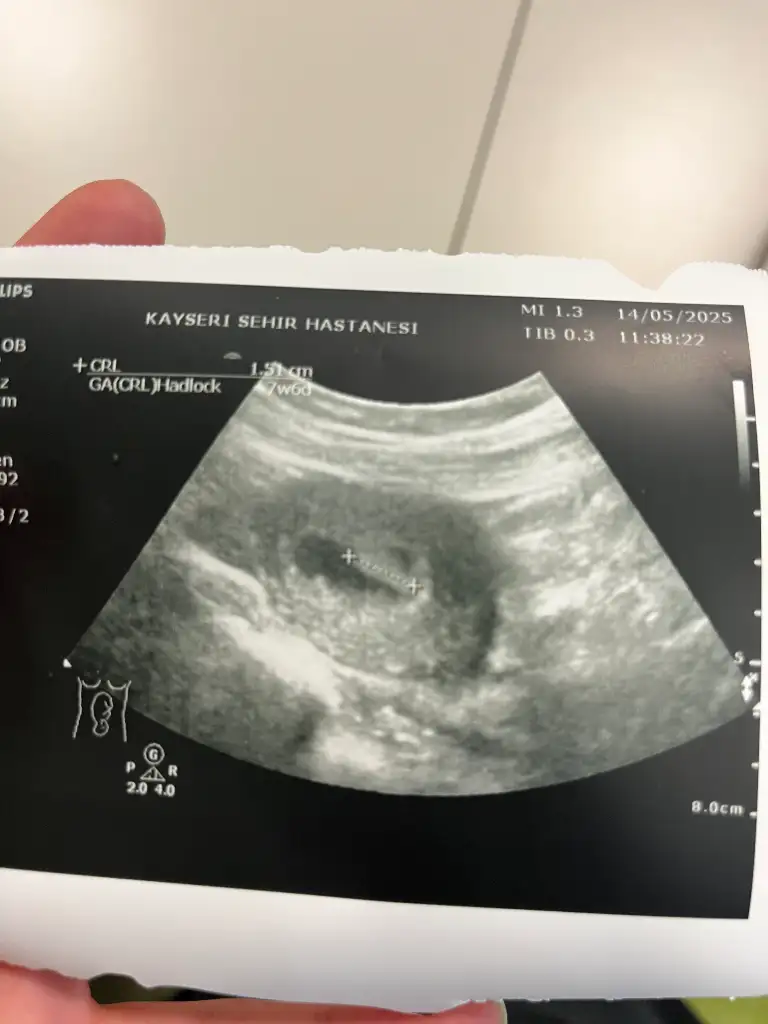

Kızlar kardeşimin bu karından bakıldı tahminde bulunabilirmisiniz rica etsem

Eklentiler

• IMG-20250520-WA0005.webp

23,4 KB · Görüntüleme: 25